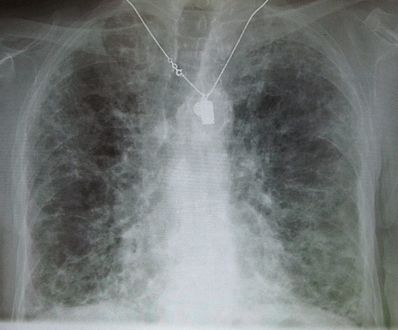

Other names: Diffuse parenchymal lung disease (DPLD)

End-stage interstitial lung disease (honeycomb lung).jpg

End-stage pulmonary fibrosis of unknown origin, taken from an autopsy

Chest radiography is usually the first test to detect interstitial lung diseases, but the chest radiograph can be normal in up to 10% of patients, especially early in the disease process.[15][16]

High-resolution CT of the chest is the preferred modality and differs from routine CT of the chest. Conventional (regular) CT chest examines 7–10 mm slices obtained at 10 mm intervals; high resolution CT examines 1–1.5 mm slices at 10 mm intervals using a high-spatial-frequency reconstruction algorithm. The HRCT therefore provides approximately 10 times more resolution than the conventional CT chest, allowing the HRCT to elicit details that cannot otherwise be visualized.[15][17]

Radiologic appearance alone, however, is not adequate and should be interpreted in the clinical context, keeping in mind the temporal profile of the disease process.[15]

Interstitial lung diseases can be classified according to radiologic patterns.[15]